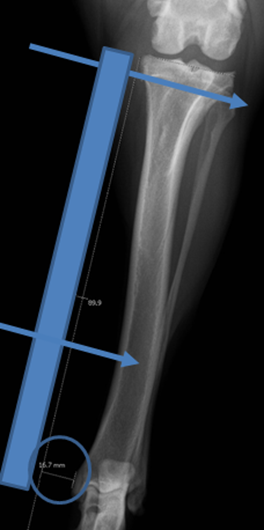

Determining the Tibial Plateau Angle (TPA)

Determining Saw Blade Radius